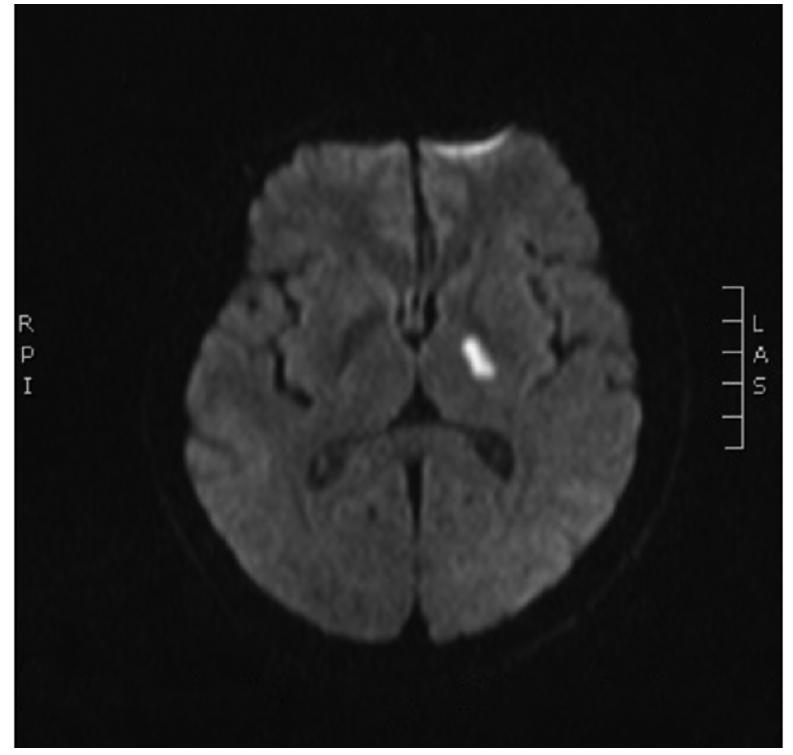

• 脑小血管病认知障碍与血清VEGF及PEDF的相关性研究

2021, 46(11):1360-1365. DOI: 10.13406/j.cnki.cyxb.002911

摘要 (84) HTML (361) PDF 2.26 M (198) 评论 (0) 收藏

摘要:目的: 探讨血清血管内皮生长因子(vascular endothelial growth factor,VEGF)及色素上皮衍生因子(pigment epithelial derived factors,PEDF)与脑小血管病(cerebral small-vascular disease,CSVD)认知障碍的关系,为筛查CSVD血管性认知功能障碍(vascular cognitive impairment,VCI)提供有效的生物学标记物。 方法: 连续性纳入2019年6月至2020年6月包头医学院第一附属医院神经内科住院的CSVD患者,完善患者临床信息资料、3.0 T头颅MRI检查包括T1加权成像、T2加权成像、液体衰减反转恢复序列、弥散加权成像及磁敏感加权成像等相关检查,采用VEGF、PEDF ELISA试剂盒检测血清VEGF、PEDF浓度。应用多变量logistic回归分析确定CSVD认知障碍的独立影响因素,运用SPSS 26.0描绘受试者工作特征(receiver operating characteristic,ROC)曲线,评价血清VEGF、PEDF浓度对CSVD认知障碍的预测价值。 结果: ①共纳入193例患者,VCI组90例(46.6%),非VCI组103例(53.4%)。2组比较显示,VCI组受教育年限、既往高血压病史、腔隙性梗死或短暂性脑缺血发作史(transient ischemic attack,TIA)、入院收缩压、舒张压、空腹血糖、血肌酐、胱抑素C、血清VEGF浓度、血清PEDF浓度与非VCI组比较,差异有统计学意义(P<0.05)。②运用多变量logistic回归模型分析显示VEGF浓度较高(优势比1.393,95%CI=1.011~1.920,P=0.042)是CSVD认知障碍的独立危险因素;而血清PEDF相对低表达(优势比0.521,95%CI=0.384~0.707,P=0.000)是脑小血管病患者认知功能障碍的独立保护因素;ROC曲线分析显示血清VEGF浓度联合PEDF浓度联合预测脑小血管病认知障碍的曲线下面积为0.769(95%CI=0.705~0.832,P<0.001),敏感性为0.911,特异性为0.612;最佳截断值为128.61 pg/mL、100.95 ng/mL,均具有较好的预测价值。 结论: 血清VEGF浓度和PEDF浓度与CSVD认知障碍存在显著相关性,血清VEGF浓度联合PEDF浓度可作为CSVD认知障碍的指标。